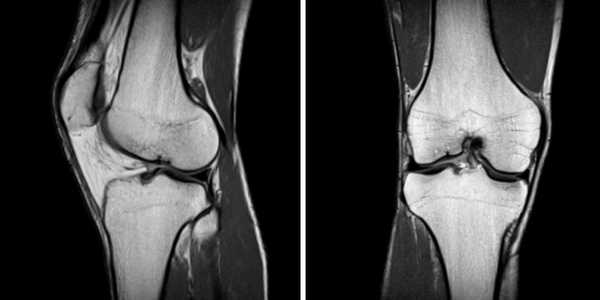

МРТ коленного сустава, разрыв передней крестообразной связки

МРТ колена: гонартроз